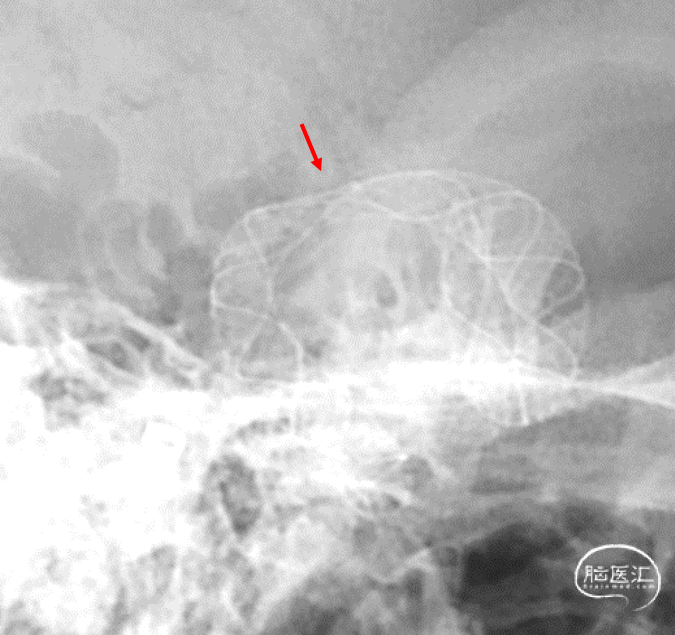

CT平扫

CTA

2024年4月1日 DSA

RICA

L ICA

L ICA 3D

AN长径9.14mm

远端血管大脑中直径2.34mm、近端颈内末端4.25mm